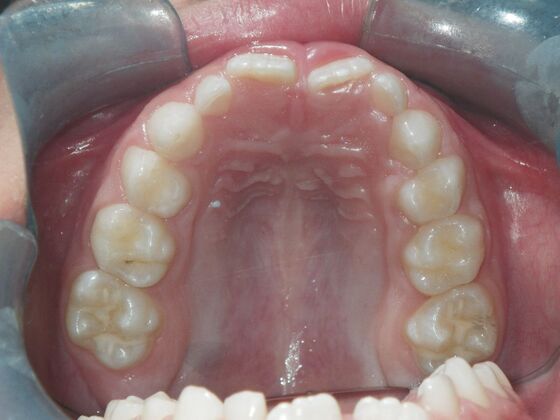

Dylan presented with a functional crossbite in which we used removable expansion appliances for 12 months, followed by bracketing of upper and lower teeth including primary ones to gain alittle more expansion, allowed to wear retainers for 6 months and then followed closely with 6 month ortho recalls and began Phase 2 treatment within 24 months and finished his ortho treatment.